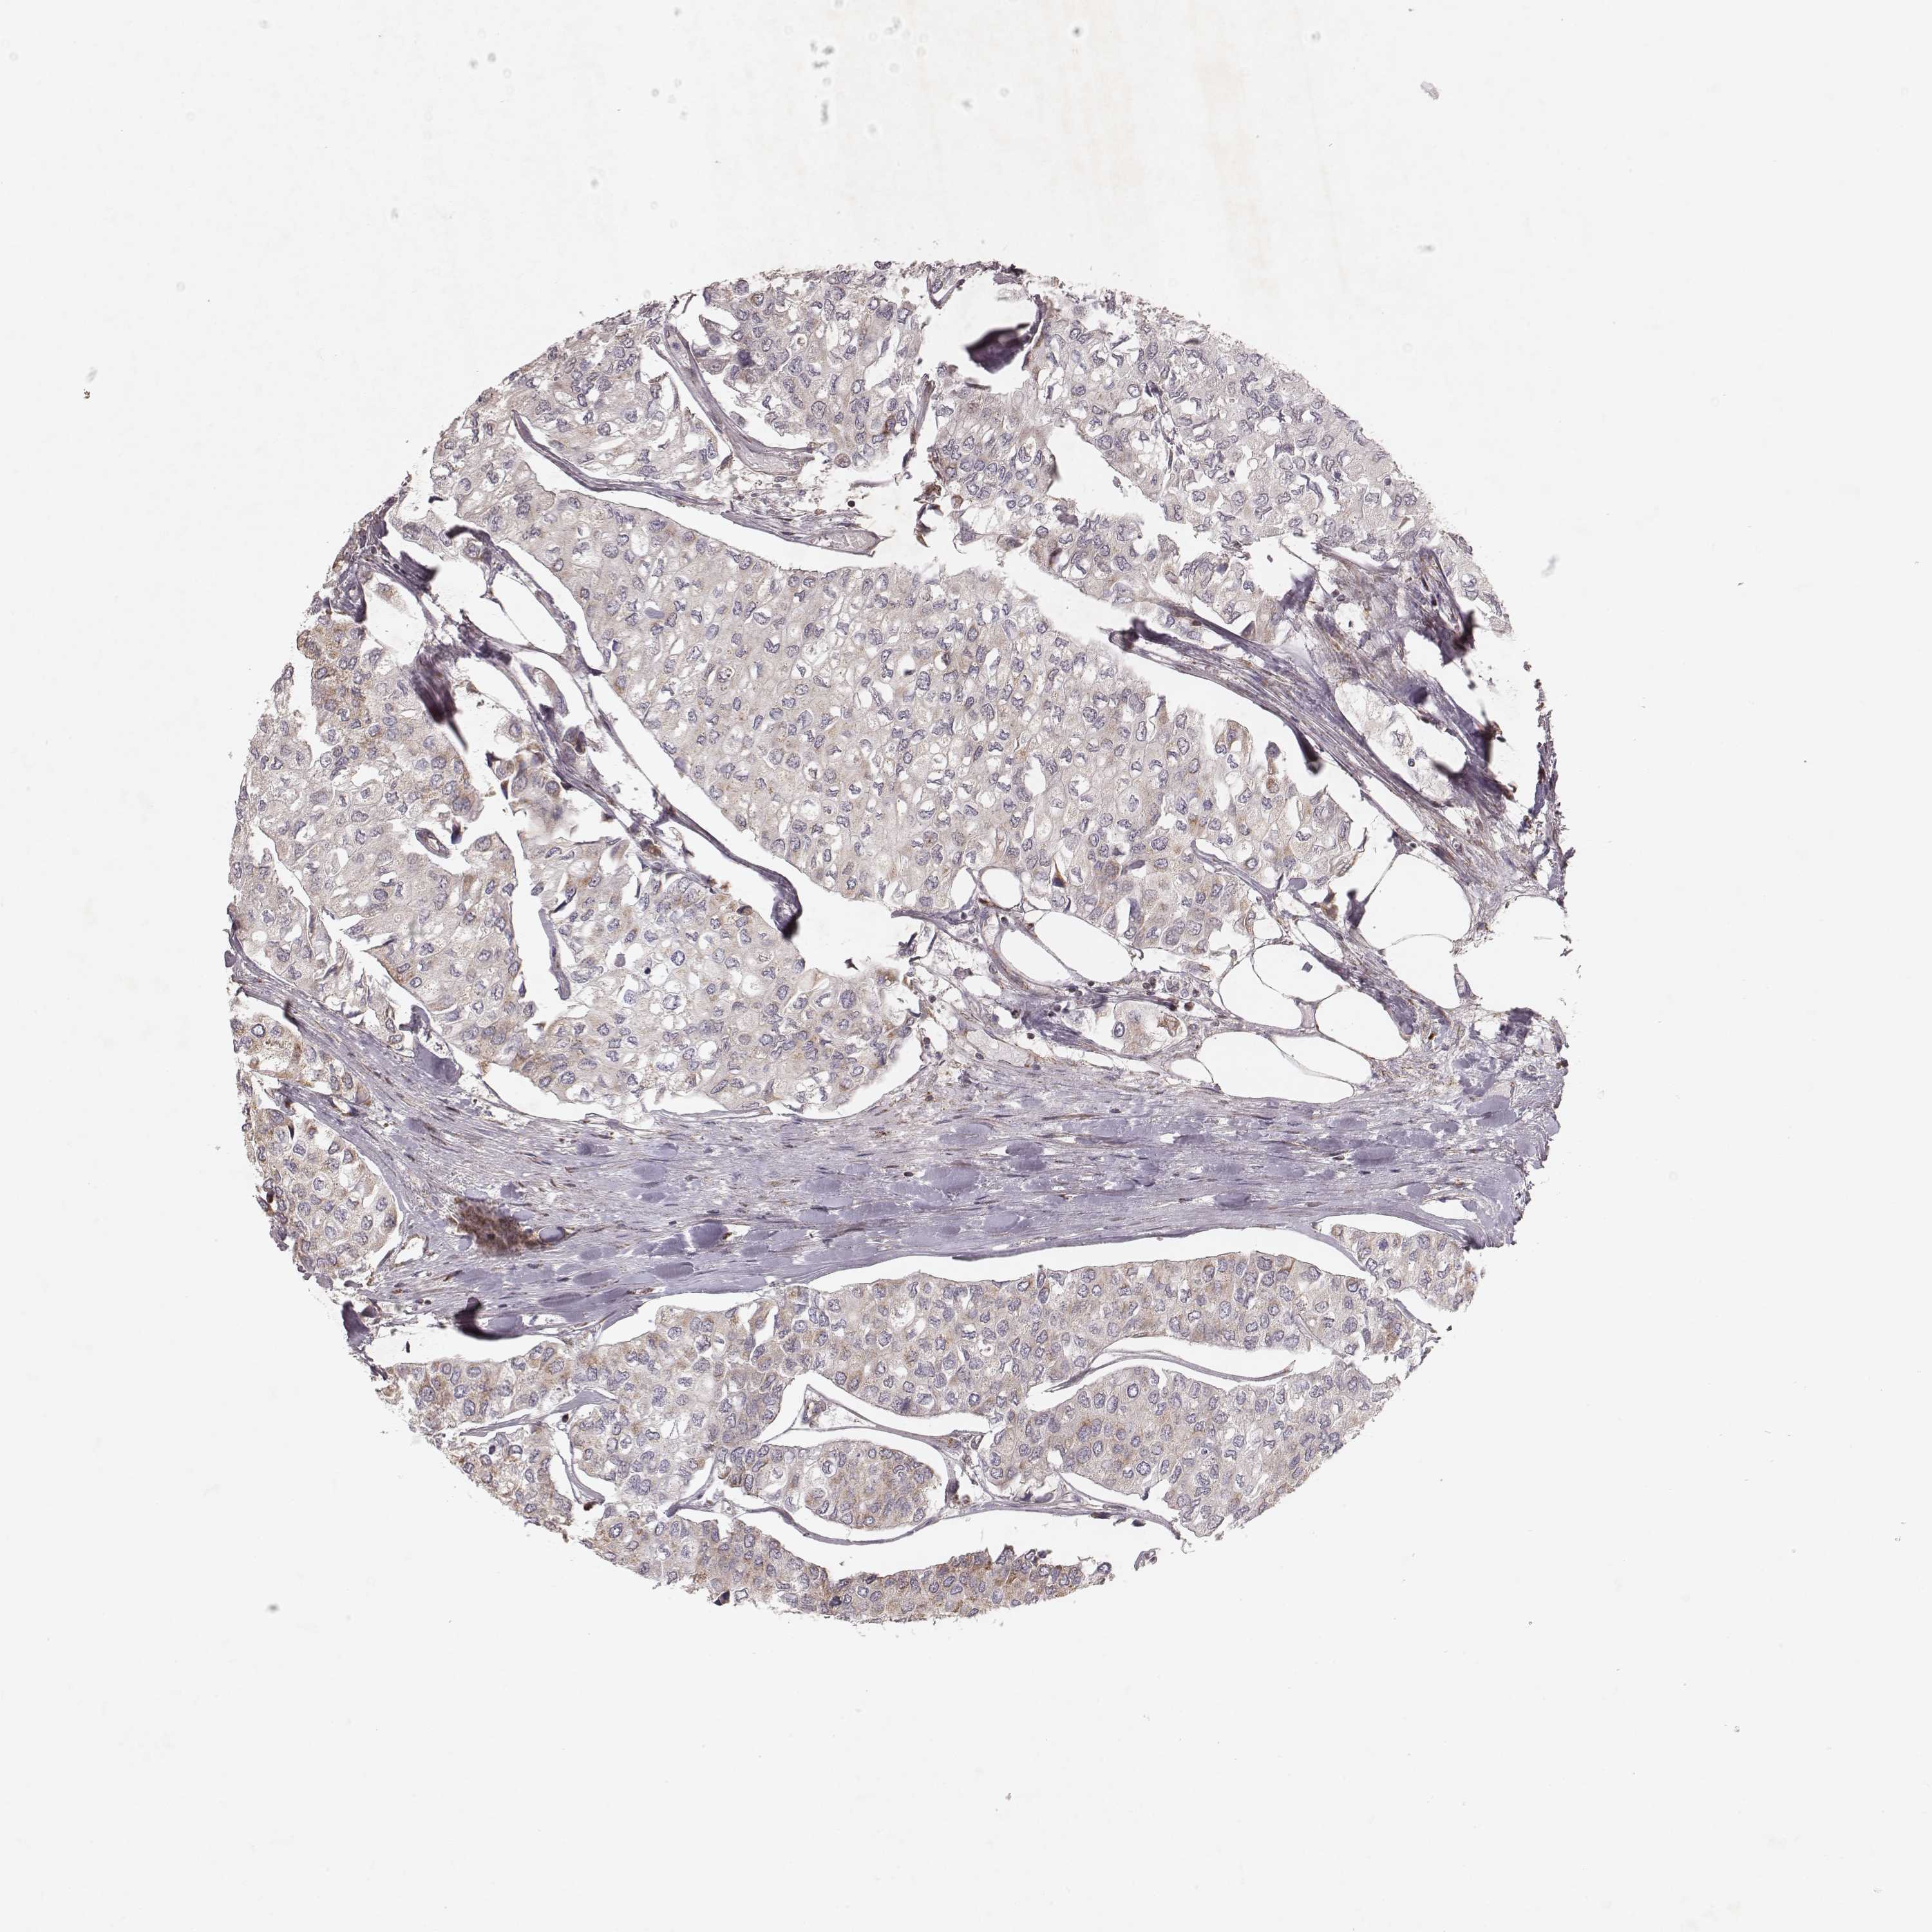

UROTHELIAL CANCER - Protein expressioni

A mouse-over function shows sample information and annotation data. Click on an image to view it in a full screen mode. Samples can be filtered based on level of antibody staining by selecting one or several of the following categories: high, medium, low and not detected. The assay and annotation is described here.

Note that samples used for immunohistochemistry by the Human Protein Atlas do not correspond to samples in the TCGA dataset.

Antibody stainingi

Antibody staining in the annotated cell types in the current human tissue is reported as not detected, low, medium, or high, based on conventional immunohistochemistry profiling in selected tissues. This score is based on the combination of the staining intensity and fraction of stained cells.

Each image is clickable and will lead to virtual microscopy that enables deeper exploration of all samples and also displays staining intensity scores, fraction scores and subcellular localization as well as patient and tissue information for each sample.

Antibody HPA059251

Antibody HPA071866

Urothelial carcinoma, High grade

Urothelial carcinoma, Low grade

Urothelial carcinoma, NOS